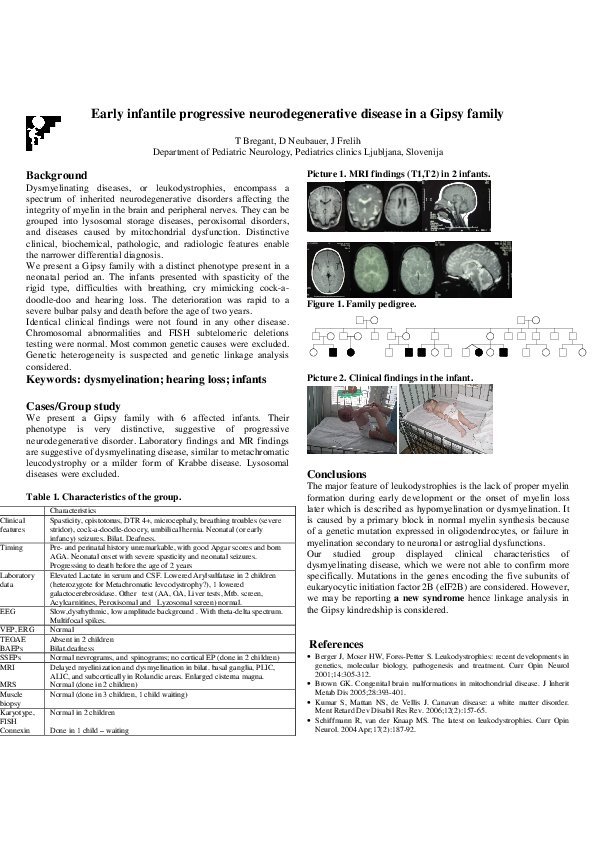

Background: Dysmyelinating diseases, or leukodystrophies, encompass a spectrum of inherited neurodegenerative disorders affecting the integrity of myelin in the brain and peripheral nerves. They can be grouped into lysosomal storage diseases, peroxisomal disorders, and diseases caused by mitochondrial dysfunction. Distinctive clinical, biochemical, pathologic, and radiologic features enable the narrower differential diagnosis. We present a Gipsy family with a distinct phenotype present in a neonatal period an. The infants presented with spasticity of the rigid type, difficulties with breathing, cry mimicking cock-a-doodle-doo and hearing loss. The deterioration was rapid to a severe bulbar palsy and death before the age of two years. Identical clinical findings were not found in any other disease. Chromosomal abnormalities and FISH subtelomeric deletions testing were normal. Most common genetic causes were excluded. Genetic heterogeneity is suspected and genetic linkage analysis considered. Cases/Group study: We present a Gipsy family with 6 affected infants. Their phenotype is very distinctive, suggestive of progressive neurodegenerative disorder. Laboratory findings and MR findings are suggestive of dysmyelinating disease, similar to metachromatic leucodystrophy or a milder form of Krabbe disease. Lysosomal diseases were excluded. Characteristics of infants encompass clinical features: spasticity, opistotonus, microcephaly, breathing troubles with a severe stridor and a distinctive cock-a-doodle-doo cry, some have umbilical hernia. They have early infancy seizures and bilat. deafness.their pre- and perinatal history was unremarkable, with good Apgar scores and born AGA. Neonatal onset is profound with severe spasticity and neonatal seizures, progressing to death before the age of 2 years Conclusions: The major feature of leukodystrophies is the lack of proper myelin formation during early development or the onset of myelin loss later which is described as hypomyelination or dysmyelination. It is caused by a primary block in normal myelin synthesis because of a genetic mutation expressed in oligodendrocytes, or failure in myelination secondary to neuronal or astroglial dysfunctions. Our studied group displayed clinical characteristics of dysmyelinating disease, which we were not able to confirm more specifically. Mutations in the genes encoding the five subunits of eukaryocytic initiation factor 2B (eIF2B) are considered. However, we may be reporting a new syndrome hence linkage analysis in the Gipsy kindredship is considered.